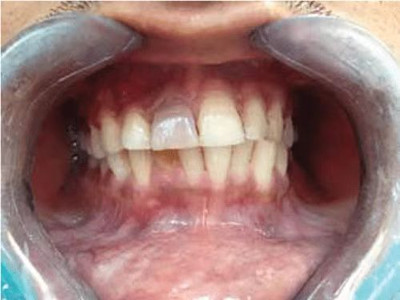

根尖囊肿生长缓慢,病人多无自觉症状。口腔检查可见患牙有龋损或其他非龋性牙体病,或牙冠变色失去光泽。叩诊可有不适感,温度测验患牙无反应。囊肿大小不等,小囊肿不易被发现。囊肿发展较大时,可见根尖部隆起,扪诊时有乒乓球感,这是由于囊肿外围只有一层极薄的骨板存在。大囊肿还可压迫牙根,使邻牙移位。